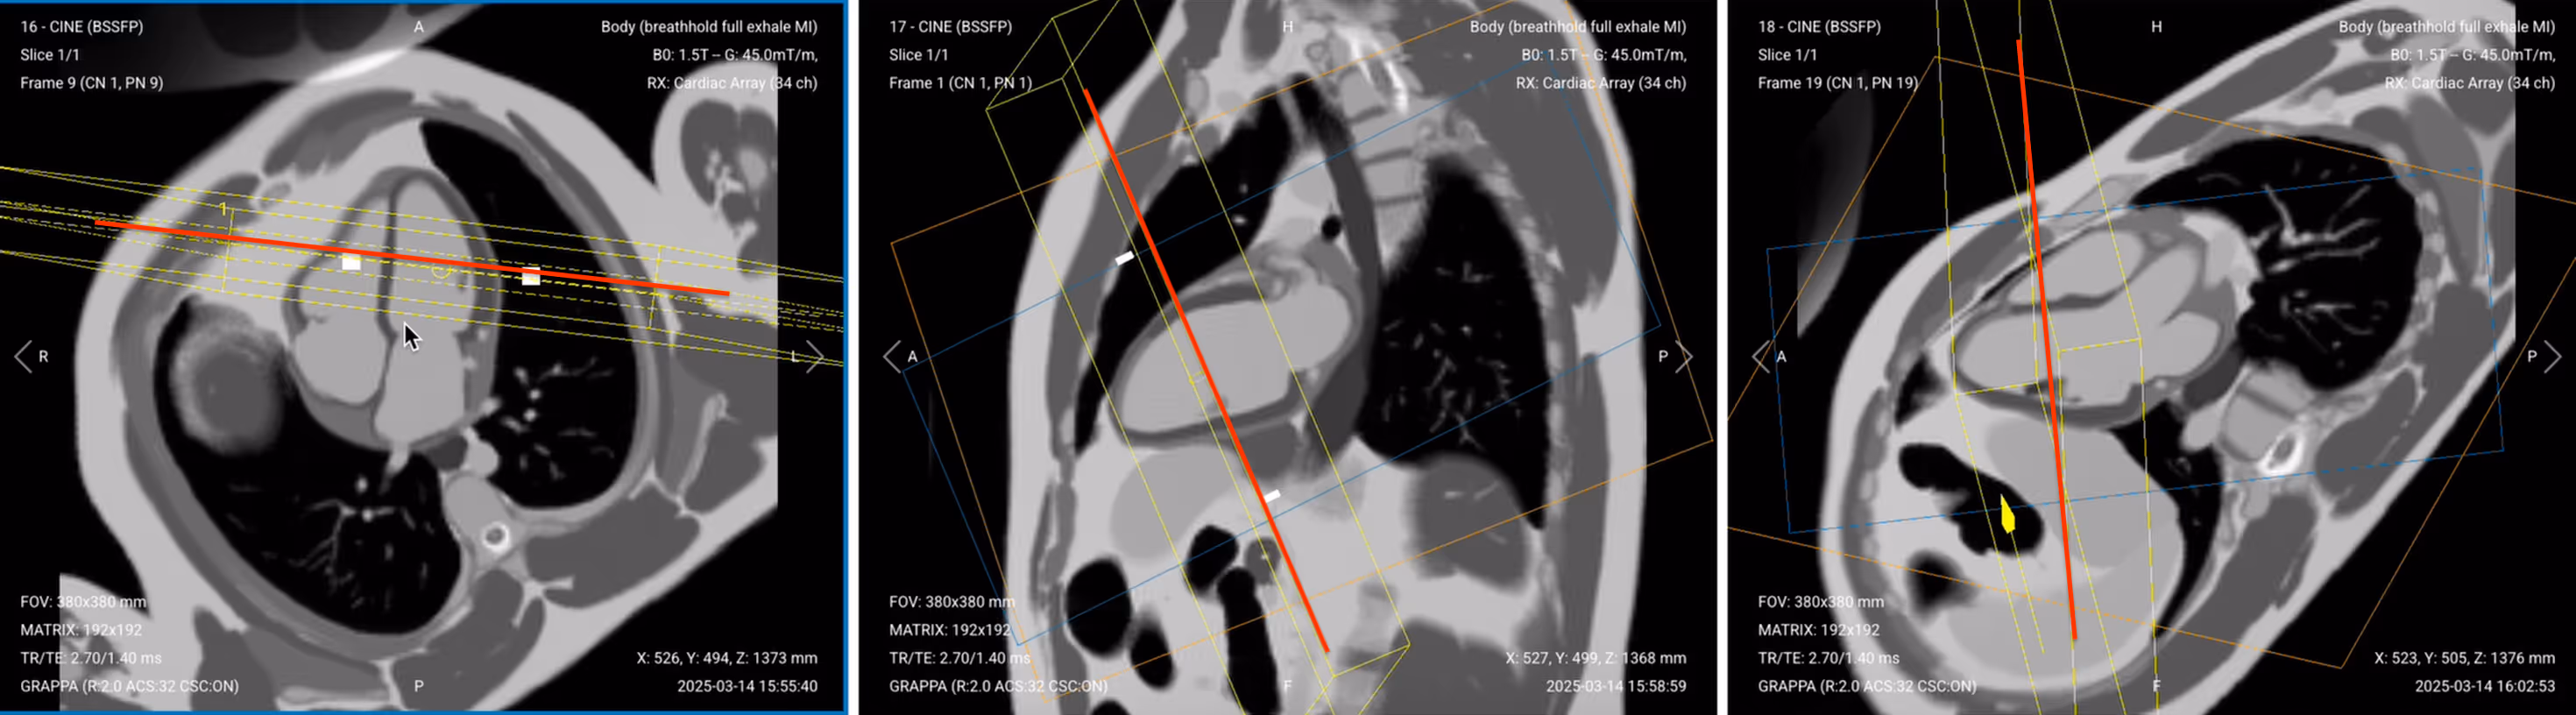

✅ Correct Planning for 4-Chamber Early Enhancement:

Correct Planning for 4-Chamber Sequence, early and late enhancement

✅ Correct Planning for 4-Chamber Late Enhancement (same as early 4-chamber):

✅ 4-Chamber Early Gadolinium Enhancement – Correct Image Example:

4-Chamber Early Gadolinium Enhancement – Correct Image Example

Things to Look for in 4-Chamber Early Enhancement:

• Assess all visible walls for dark MVO zones

• Both ventricles should be clearly visible

• Look for any pericardial enhancement suggesting inflammation